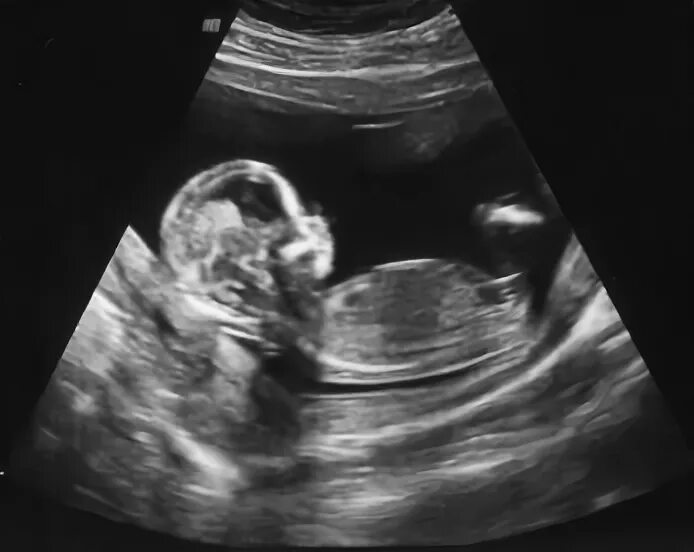

Беременность 12 недель ощущения в животе